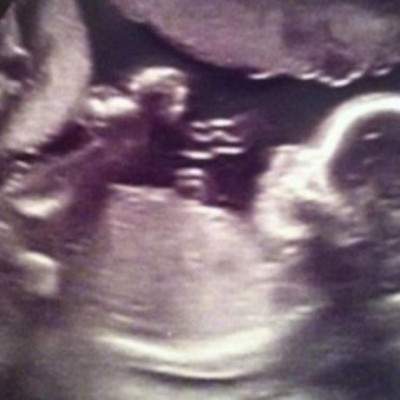

Πολύ τρυφερό! Υπέρηχος δείχνει έναν «άγγελο» να προσέχει την αγέννητη κόρη της (εικόνα)